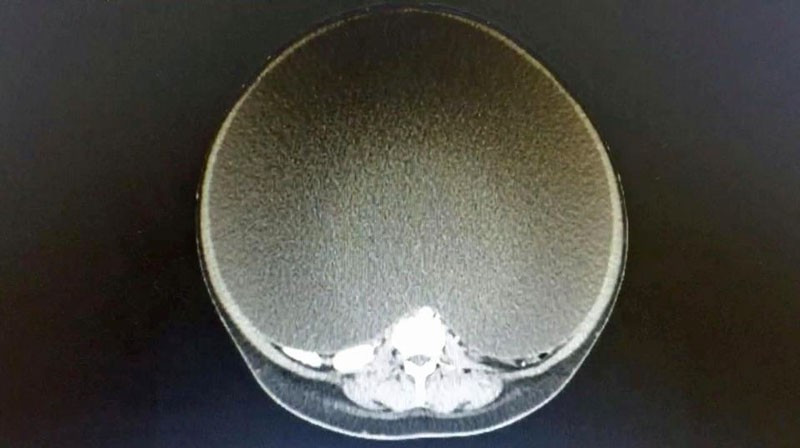

24 yaşındaki kadın hastanede Dr. Erik Hanson Viana ile tanıştı. Hemen kadının röntgenini çeken doktor, gördükleri karşısında şaşırdı kaldı. Kadının midesinde devasa boyutlara ulaşan over kisti varmış.

Kist zamanla o kadar büyümüş ki kadının organlarını sıkıştırmaya ve zarar vermeye başlamış. Kadının her an kalp krizi geçirme riski vardı. Acilen operasyona girmesi gerekiyordu.Dr. Viana, Daily Mail’e “Bugüne dek çıkardığım en büyük kistti. O kadar büyüktü ki midesinin %95’ini kaplıyordu. Kist dairesel olarak hesaplanınca 157 cm’ye varabiliyordu” dedi.